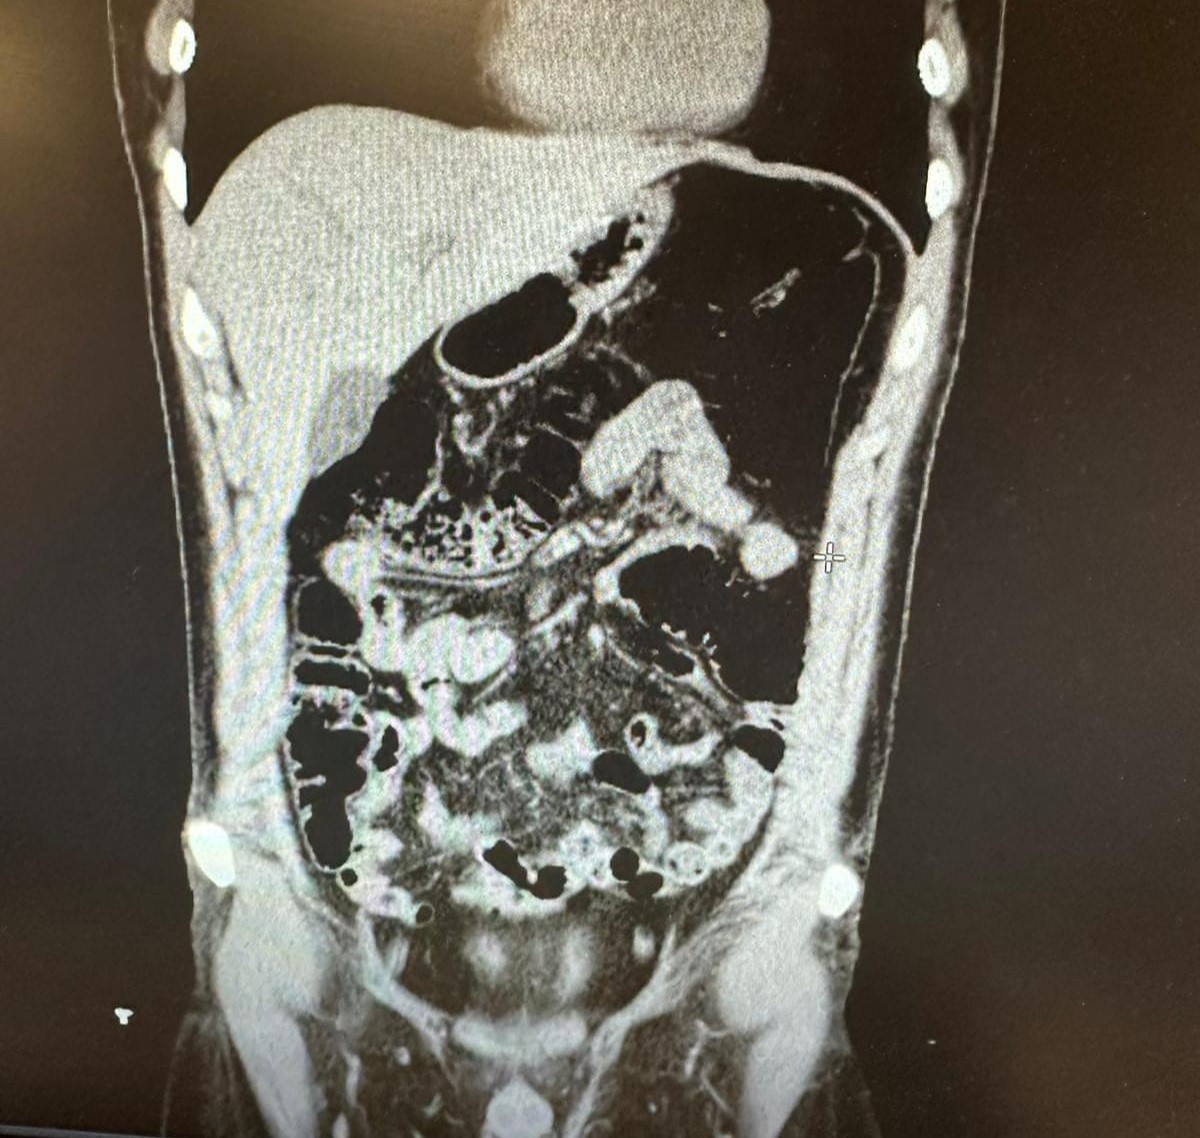

Ekiplerin titizlikle yürüttüğü saha çalışmalarında uyuşturucu kuryeliği yapan İran uyruklu bir şahıs tespit edildi. Polis, şüphelinin Konya’da gizlendiği adresi tespit ederek operasyon düzenledi. Şüpheli ve beraberindeki 4 kişi gözaltına alındı. Şüphelinin uyuşturucu yuttuğunu ifade etmesi üzerine hastaneye kaldırıldı. Şüpheli, 2 gün boyunca polis nezaretinde hastanede gözlem altında tutularak midesinde kapsüller halinde bulunan eroin maddesi doğal yollarla dışarı çıkarıldı.

Konya’da konakladıkları evin tespit edilmesiyle 1’i İran uyruklu 5 şüpheli yakayı ele verdi. İran uyruklu Vahıd Farhang Gangachı’nin midesinde 300 gram, gizlendiği adreste ise Narkotik köpeği Alex ile yapılan aramada ise toplam 6 parça halinde 1 kilogram eroin, bir miktar metamfetamin ve bir miktar uyuşturucu hap ele geçirildi.